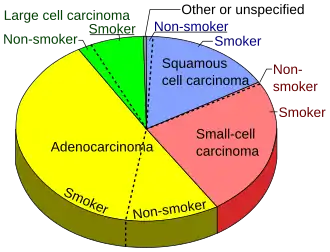

Small cell lung carcinoma accounts for 15% of lung cancers in the United States.[83] Small cell lung cancer occurs almost exclusively in smokers – most commonly in heavy smokers and rarely in non-smokers.[84][85]

- ^ Smokers defined as current or former smokers of more than 1 year of duration. See image page in Commons for percentages in numbers. Reference:

- Kenfield SA, Wei EK, Stampfer MJ, Rosner BA, Colditz GA (June 2008). "Comparison of aspects of smoking among the four histological types of lung cancer". Tobacco Control. 17 (3): 198–204. doi:10.1136/tc.2007.022582. PMC 3044470. PMID 18390646.